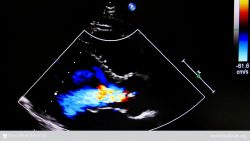

Tricuspid Regurgitation

Tricuspid regurgitation is also called tricuspid insufficiency or tricuspid incompetence. It means there is a backflow of blood from the lower-right chamber (the right ventricle) to the upper-right chamber (the right atrium), either because of a damaged tricuspid valve or an enlarged right ventricle. Blood is pushed back into the major veins instead of moving forward into the lungs, where it can pick up oxygen.